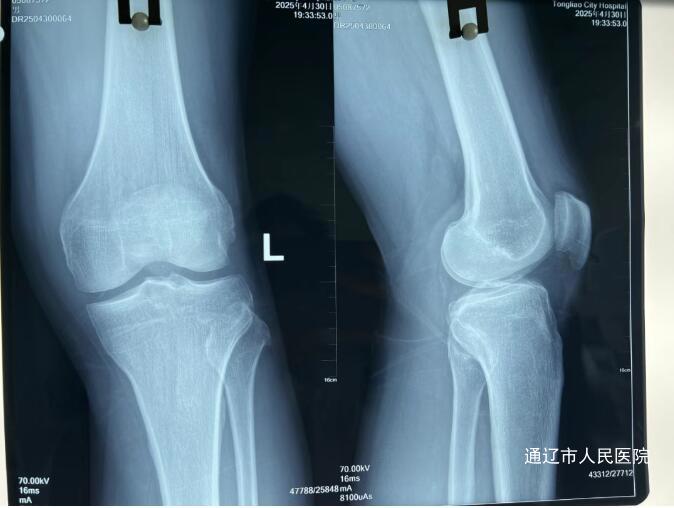

术前

(前交叉韧带损伤MRI图像)